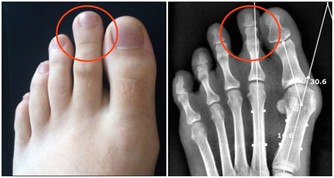

02.男性的鼻毛為什麼會“竄”出來?鼻毛旺盛代表什麼?看完漲知識了

2.荷爾蒙分泌旺盛

由於荷爾蒙旺盛而刺激雄性激素分泌,

荷爾蒙旺盛程度跟遺傳基因以及飲食脫離不了乾系,長期高動物蛋白飲食可刺激雄性激素分泌,